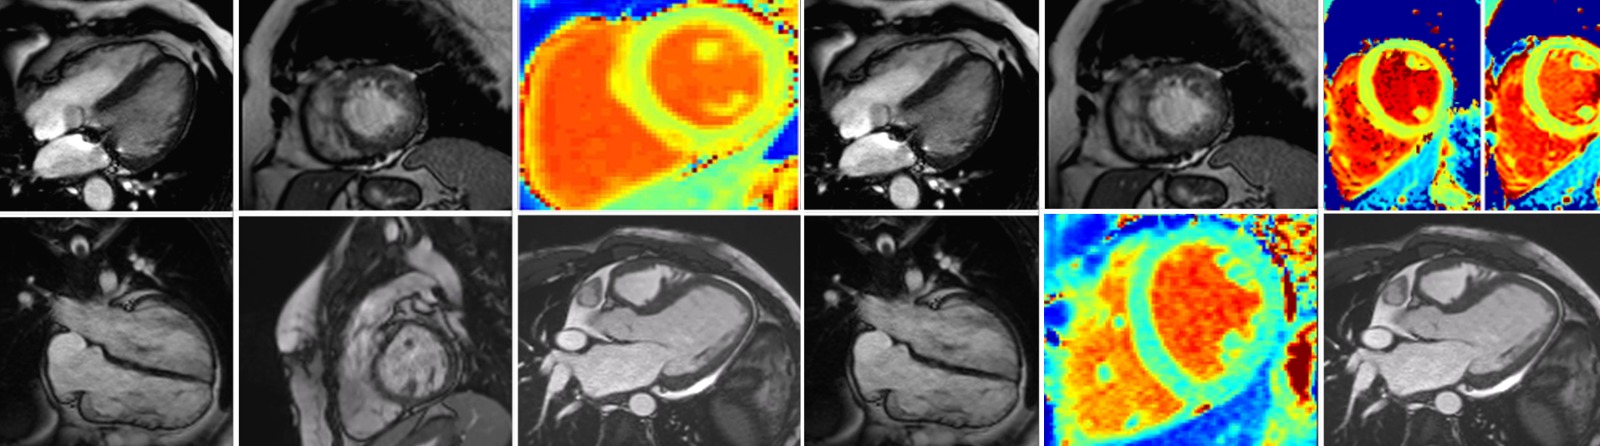

Rezonanța magnetică cardiovasculară (Cardio-RM) este cea mai avansată metodă imagistică de evaluare a funcției inimii. La Emerald, investigația este realizată de o echipă formată dintr-un medic radiolog cu experiență și un medic cardiolog specializat în RM cardiovasculară, în timpul acesteia fiind preluate peste 1500 de imagini de pe inimă, cu ajutorul unui aparat de ultimă generație, mai rapid, mai precis și mai silențios. Rezonanţa magnetică este o scanare nedureroasă și inofensivă, ce permite să privim în interiorul corpului fără utilizarea razelor X. Cu ajutorul unui magnet şi a undelor radio obţinem imagini detaliate, de foarte bună calitate cu privire la structura şi funcţia inimii.

Centrul Medical Emerald se află în acest proces de certificare europeană de peste 8 luni de zile, existând o listă foarte strictă de criterii, de la echipamentele tehnice și software folosite la acreditările echipei medicale, numărul de investigații realizate și chiar tipurile de secvențe utilizate, fiind obligatorii o înaltă calitate a examinărilor și acoperirea unei arii mari de patologii, incluzând patologii congenitale, cardiomiopatii, miocardită sau boală cardiacă ischemică.